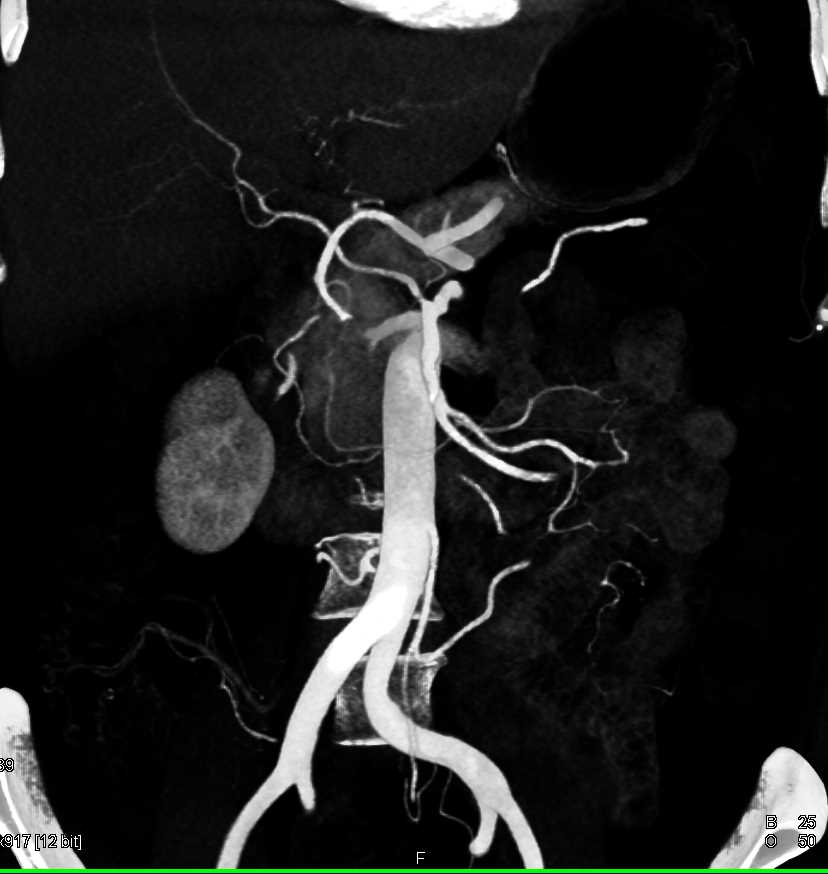

Neuroendocrine Tumor Body of Pancreas